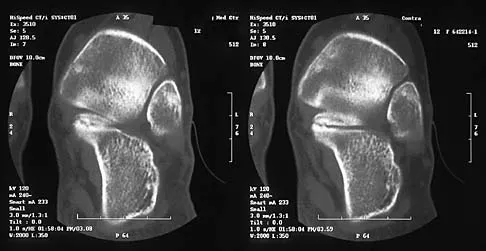

Figures 45a and 45b show the radiographs of a 14-year-old boy who sustained a distal radius fracture while playing hockey. After 1 year the patient is asymptomatic. Follow-up and comparison radiographs and an MRI scan are shown in Figures 45c and 45d. What is the next most appropriate step in management?

Explanation

The patient sustained a growth plate fracture of the distal radius and ulna. Although treated with closed reduction and casting, the follow-up radiographs demonstrate shortening of the radius in comparison to the ulna, and the MRI scan confirms thinning of the distal radius growth plate and bony bars consistent with a growth arrest. At this time, the discrepancy in length is too minor to consider lengthening of the radius; in addition, excision of a physeal bar with minimal growth potential is not likely to restore the gross discrepancy. Ulnar styloid fractures are rarely symptomatic and do not require treatment in the asymptomatic patient. Closure of the distal ulna growth plate will prevent further discrepancy between the radius and ulna. Vanheest A: Wrist deformities after fracture. Hand Clin 2006;22:113-120.